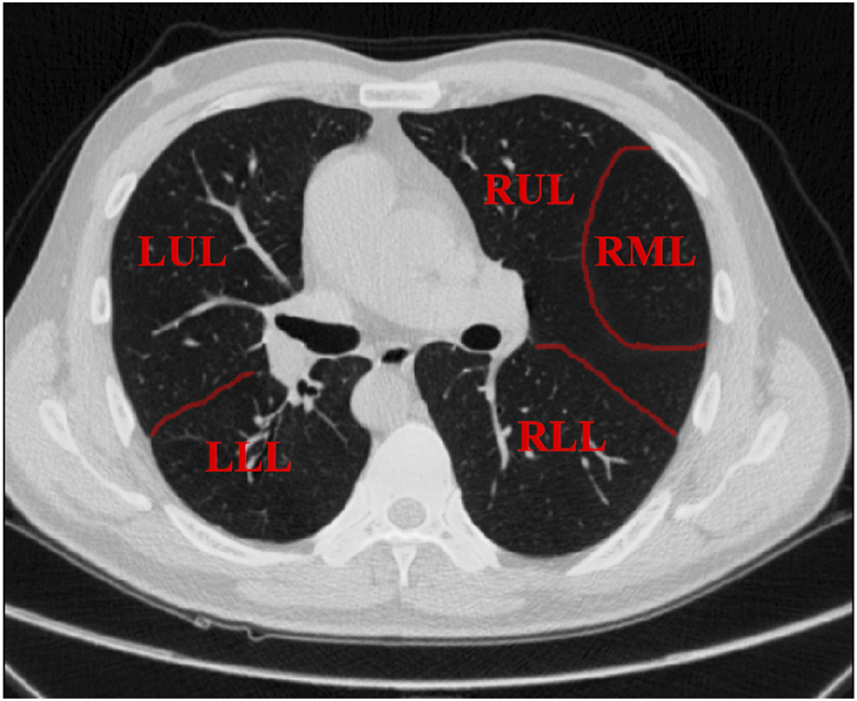

Lung cancer is the most prevalent cancer in China [1] and the most prevalent cancer in the world [2]. The clinicians must use the patient’s pathological cells as the “gold standard” for the diagnosis and grading of lung cancer [3]. Normally, the pathological cells will be obtained by a lung biopsy puncture procedure. In order to enable the surgeon to accurately insert the biopsy needle into the lobe of the lung where the tumour is located, pre-operative surgical planning requires precise segmentation of the five lobes of the lung [4]. The lungs are divided into five lobes in Figure 1, including the three lobes of the right lung, namely, the right upper lobe (RUL), the right middle lobe (RML) and the right lower lobe (RLL), are separated by a small crack and a large crack, while the two lobes of the left lung, namely, the left upper lobe (LUL) and the left lower lobe (LLL), are separated by a large crack.